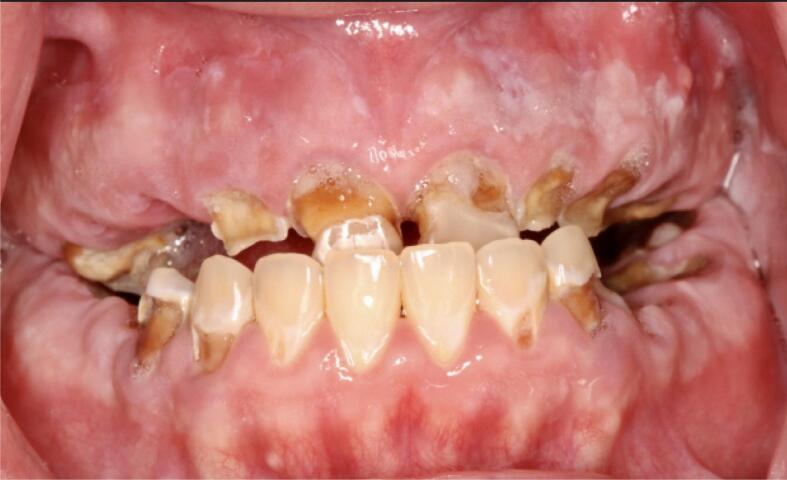

Fig. 5.

Pre-treatment intraoral frontal view of a crystal meth user. Loss of VDO, reverse articulation, residual roots, and rampant brown carious lesions are shown.